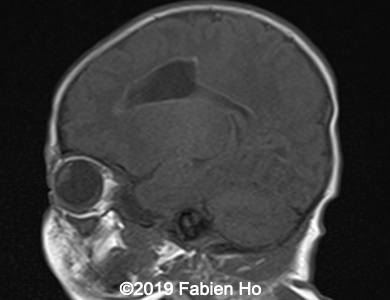

Images 12-16: we performed a second fetal brain MRI at 32 weeks, which showed the same findings as the postnatal neonatal brain MRI as follows:

The evolution of the images is typical of a clastic lesion: after resorption of the ischemic tissue and hematoma, there was now a focal porencephaly with hemosiderin tattooing on its margins. Conversely, persistence of the same MRI findings would have indicated an hypercellular brain tumor, which could have been a differential diagnosis.

The child was delivered normally at 38 weeks of pregnancy. Neonatal clinical examination was normal. Neurological development will be under close watch for the next few years.